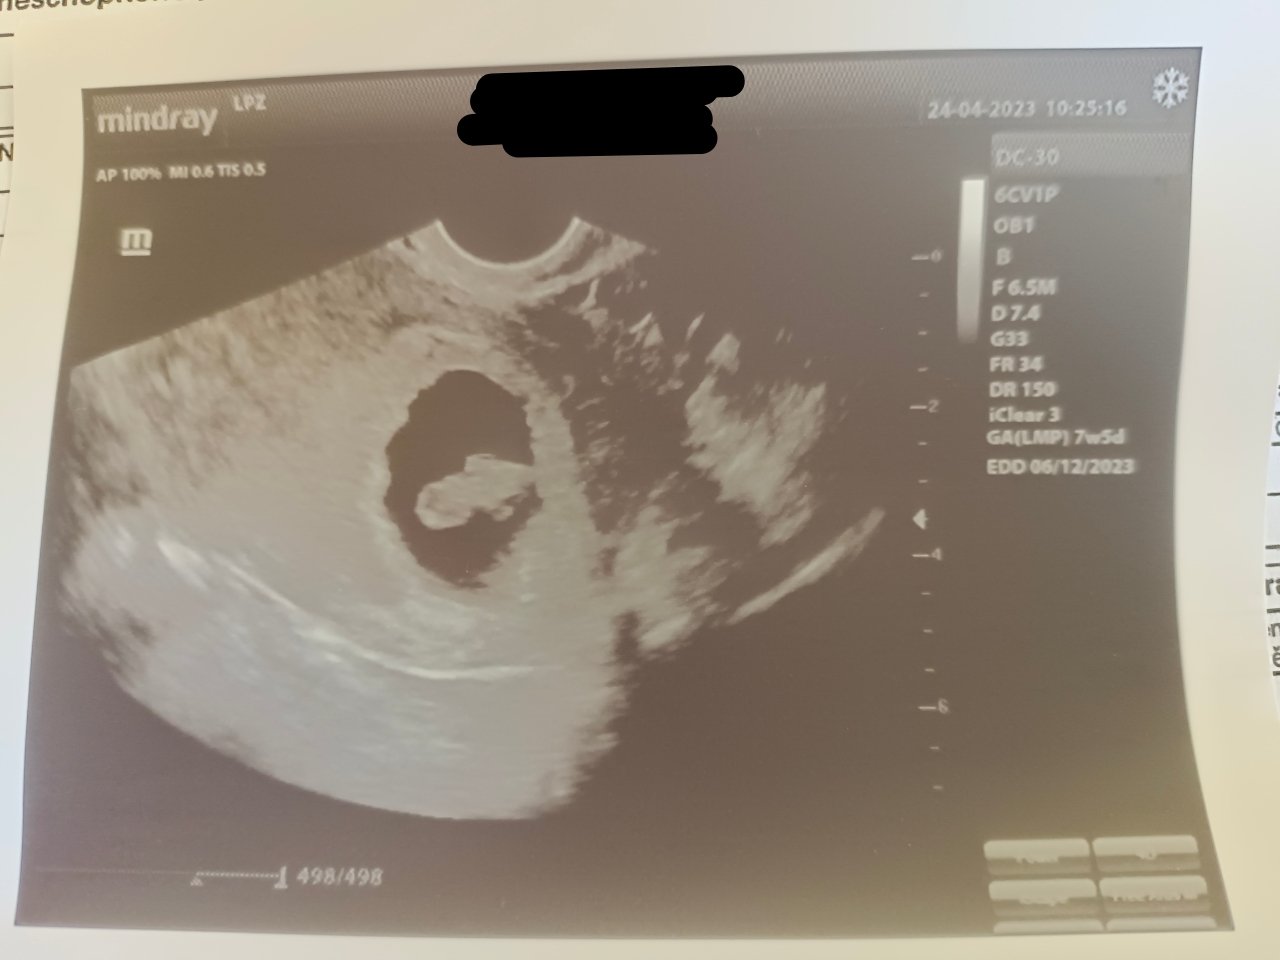

Ahojte,vidíte tam niečo?ja som videla zo začiatku akoby dušíka...poprípade skúste mi to dať do negatíva..Ďakujem